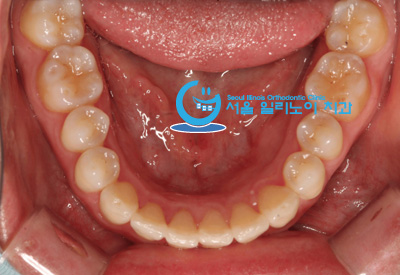

덧니교정 – 발치없는 덧니교정10 (투명교정장치 & no brace)